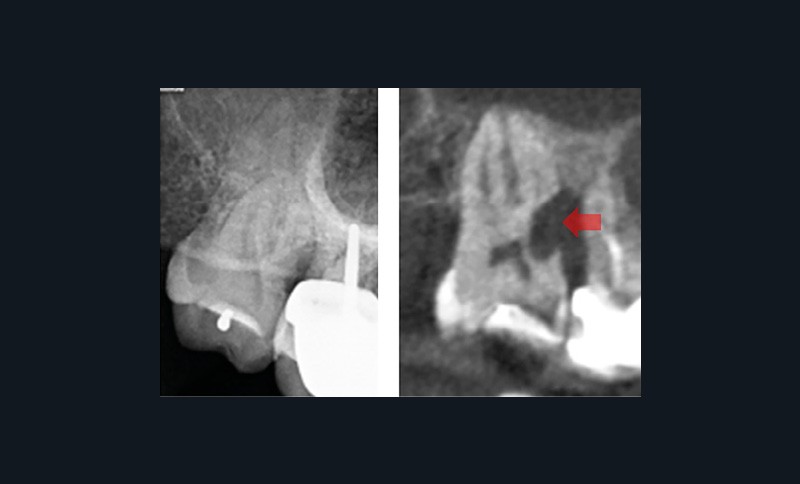

Lors de la consultation en endodontie, l’interrogatoire et l’examen clinique sont prépondérants dans l’établissement du diagnostic. Celui-ci nécessite la plupart du temps la prise de clichés radiographiques. Selon la Haute Autorité de Santé, la radiographie rétro-alvéolaire est même un prérequis obligatoire à tout traitement endodontique. Cependant, les résultats des tests cliniques, tout comme l’analyse sur radiographie rétro-alvéolaire, peuvent être subjectifs. Le CBCT pallie en partie ces limites par une analyse tridimensionnelle de l’anatomie canalaire et de ses rapports avec le milieu extra-radiculaire, permettant d’affiner le diagnostic. Il permet de détecter 60,9 % des radio-clartés péri-apicales, contre seulement 39,5 % avec une radiographie rétro-alvéolaire [2]. Cette aide au diagnostic explique pourquoi les endodontistes interrogés modifiaient leur diagnostic étiologique dans 55 % des cas présentés et leur prise en charge dans 49 % des cas lorsqu’ils avaient accès au CBCT [3]. On comprend alors qu’en cas d’incertitude ou face à une anatomie canalaire complexe, la Société Européenne d’Endodontie et l’Association Américaine d’Endodontie recommandent de réaliser un examen complémentaire 3D afin d’éviter toute perte de chance pour le patient. Cela est particulièrement pertinent pour affiner le diagnostic et retrouver une dent causale lorsque le diagnostic étiologique est compliqué (fig. 1) ainsi que pour exclure une pathologie d’origine non endodontique (fig. 2).